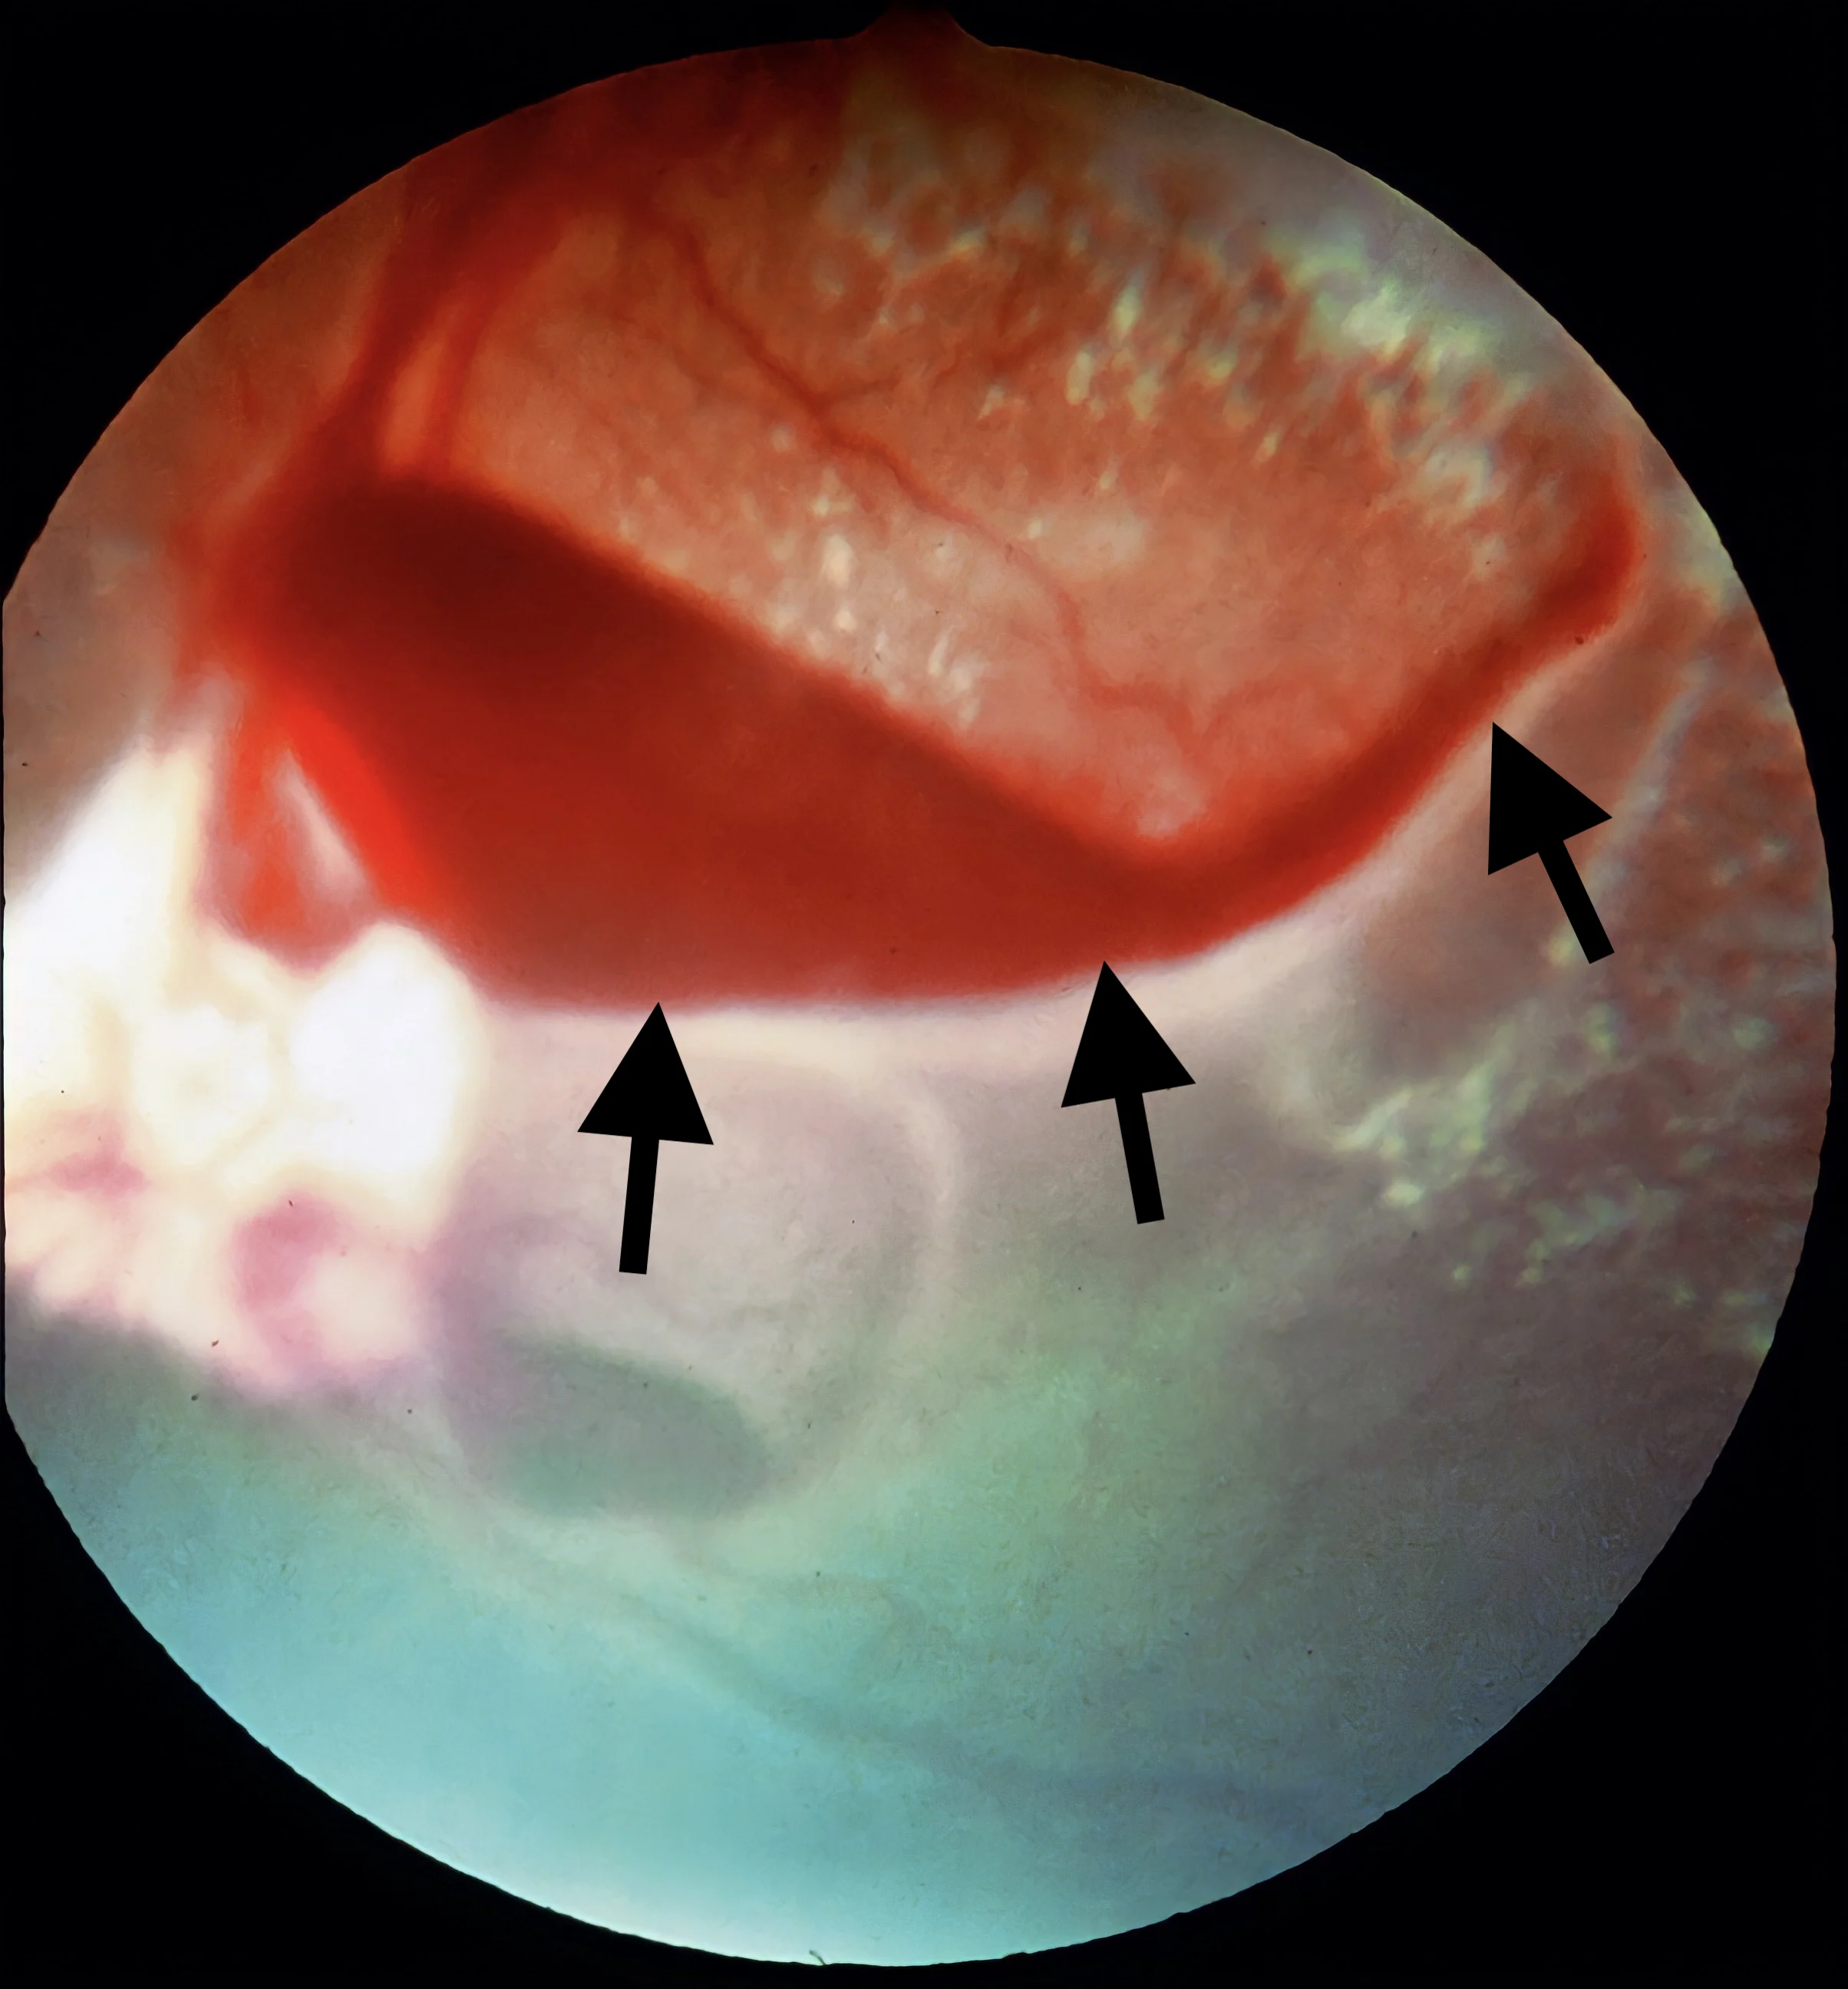

Intraocular image showing retina in background and arrows pointing to vascular red structure in foreground.

FIGURE 3

Fresh, characteristic keel-boat–shaped preretinal hemorrhages (arrows) between the retina and vitreous humor secondary to systemic hypertension in a dog